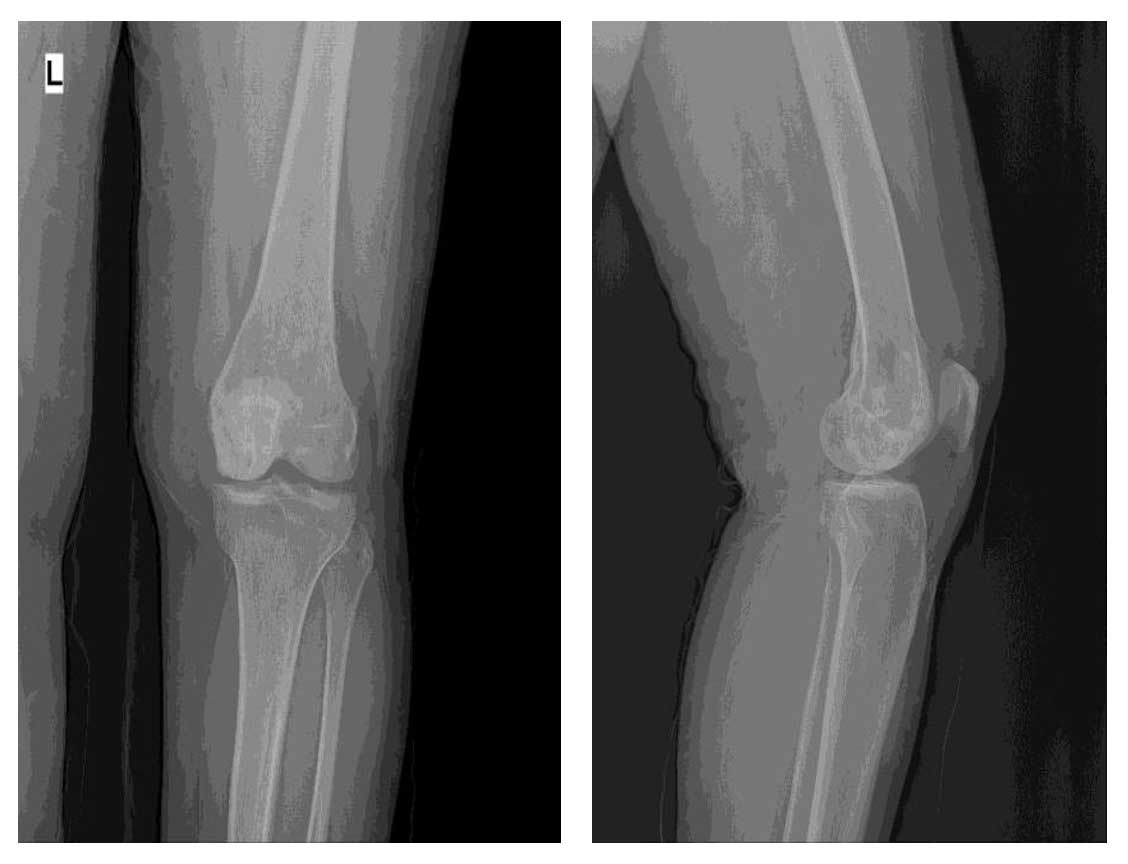

Ameliyat Öncesi: Röntgende distal femurda düzensizlik ve harabiyet görülmekte.